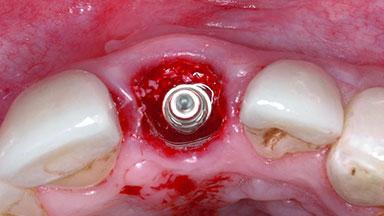

Replacement of a Failing Upper Left Central Incisor: Immediate Placement of an RC Bone Level Implant and Provisionalization

A healthy 23-year-old female patient was referred for a consultation on replacing tooth 21 with an implant-supported restoration. The patient had recently moved to the area and reported a history of endodontic and periodontal treatment for tooth 21. The tooth had been deemed non-restorable by her previous periodontist but since she was going to be moving, he recommended consulting to a dentist in her new city to continue her treatment. A review of her medical history yielded no significant findings and no known drug allergies. The analysis of her smile revealed a medium to high symmetrical smile line and a slightly discolored tooth 21.

Placement Protocol Immediate implant placement

Tooth Site Maxillary incisor or canine

Socket Morphology Single-root socket

Socket Integrity Damage to one or more bone walls

Bone Volume Damage to one or more socket walls